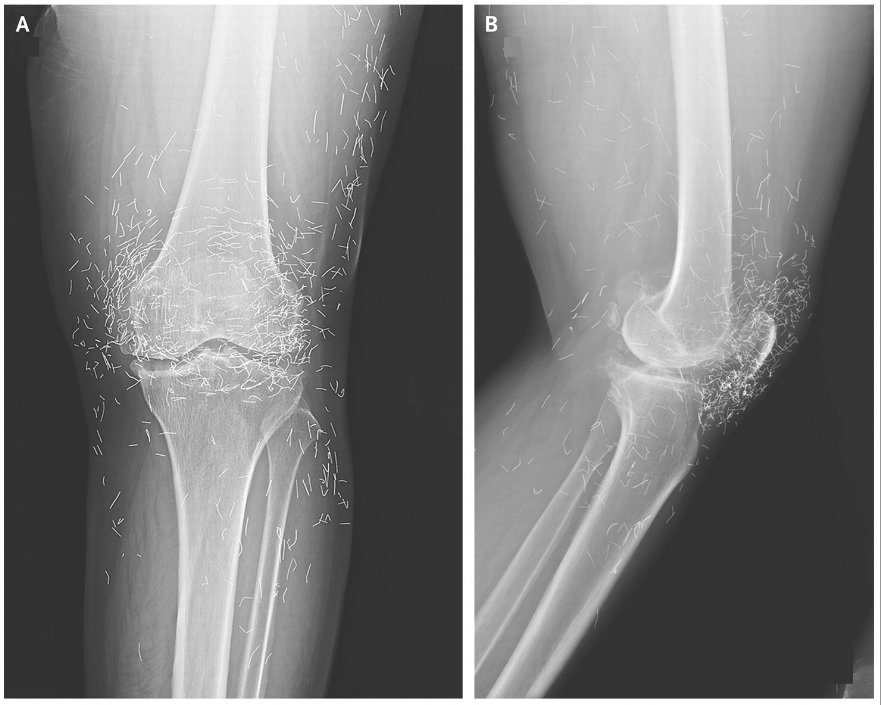

4. Acupuncture led to joint injury

A woman with osteoarthritis of the knee began getting acupuncture regularly when her pain medications started causing bad stomach issues. But her knees then became very sore, and she went to a hospital to be examined. X-rays revealed areas of her joints and shinbones where the bone tissue had thickened and spurs had formed. Additionally, hundreds of tiny flecks could be seen around both knee joints. It turned out that the woman’s acupuncturists had left golden threads inside her knees on purpose as part of her treatment. In other cases, these threads have caused cysts and tissue damage, which can happen when they migrate through the body.